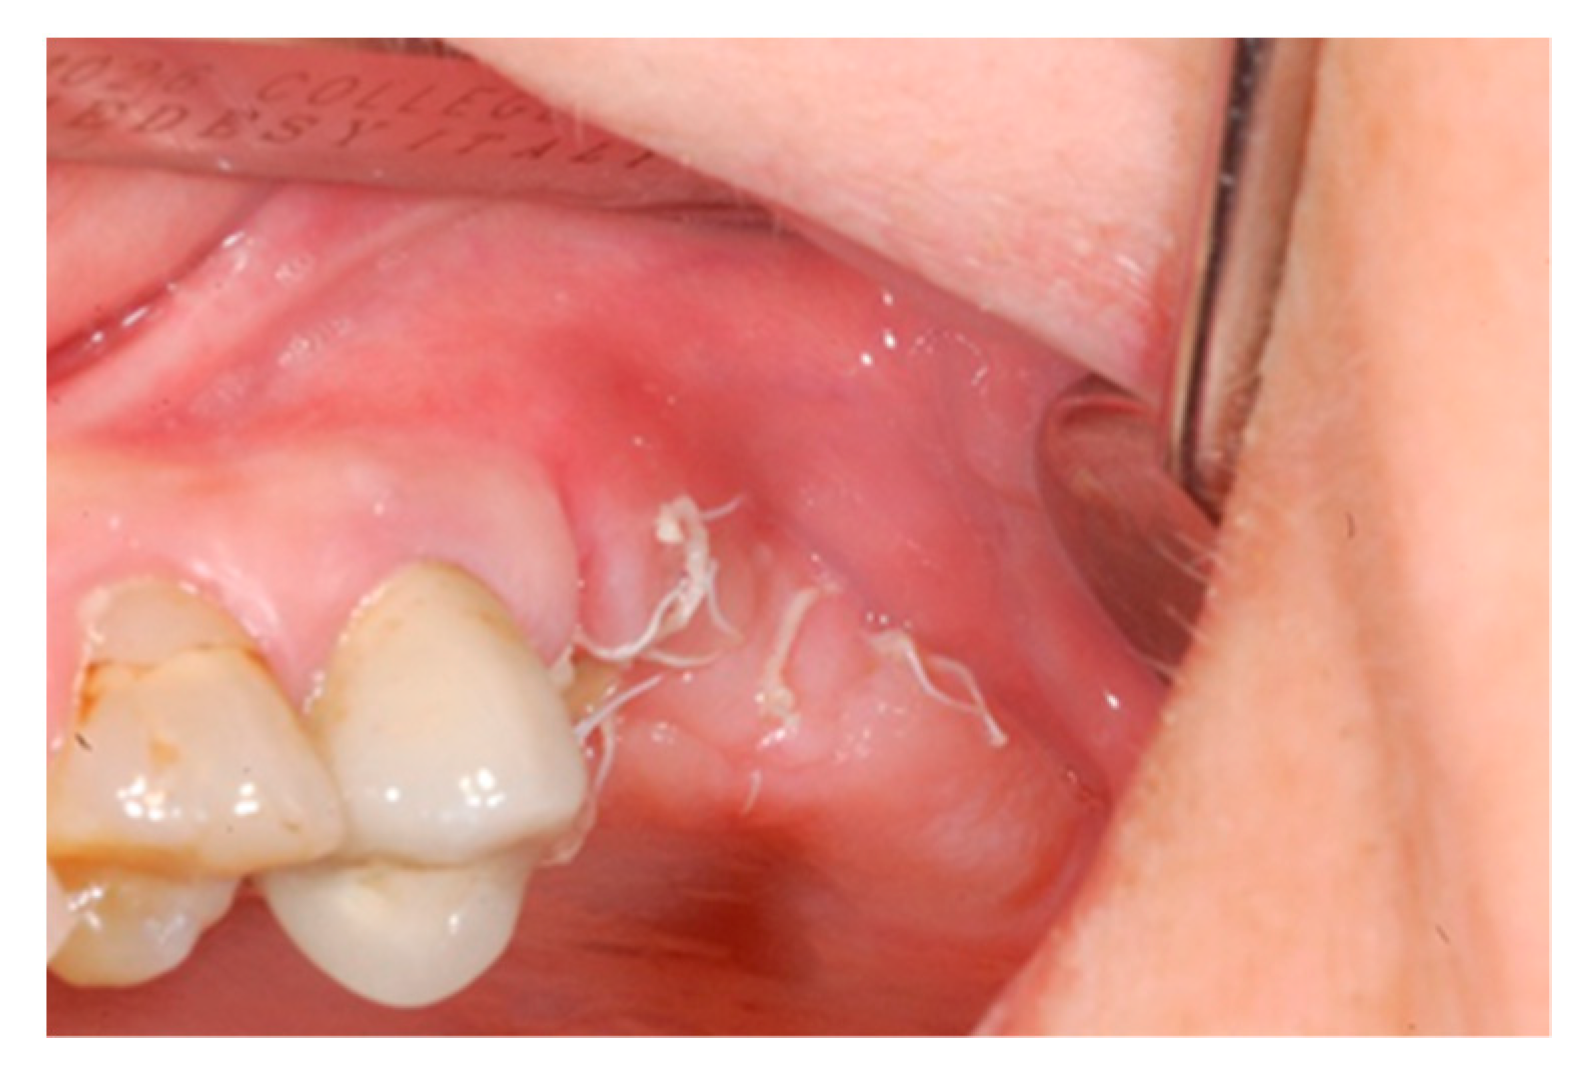

Ten days after the extraction and socket preservation, the patient was recalled for the suture removal. The clinical observation showed the occurrence of physiological healing without any complication (Figure 6 and Figure 7).

Figure 6.

Vestibular intraoperative view of the oral mucosa 10 days after tooth extraction and socket preservation. Soft tissues appeared completely healed with no signs of bone exposition, considered as a clear sign of bisphosphonate-related osteonecrosis of the jaw (BRONJ).